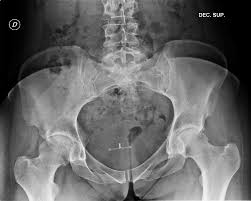

2) X-ray 검사

관절 간격이 좁아지거나 변형된 경우 퇴행성 관절염 가능성을 확인할 수 있습니다.